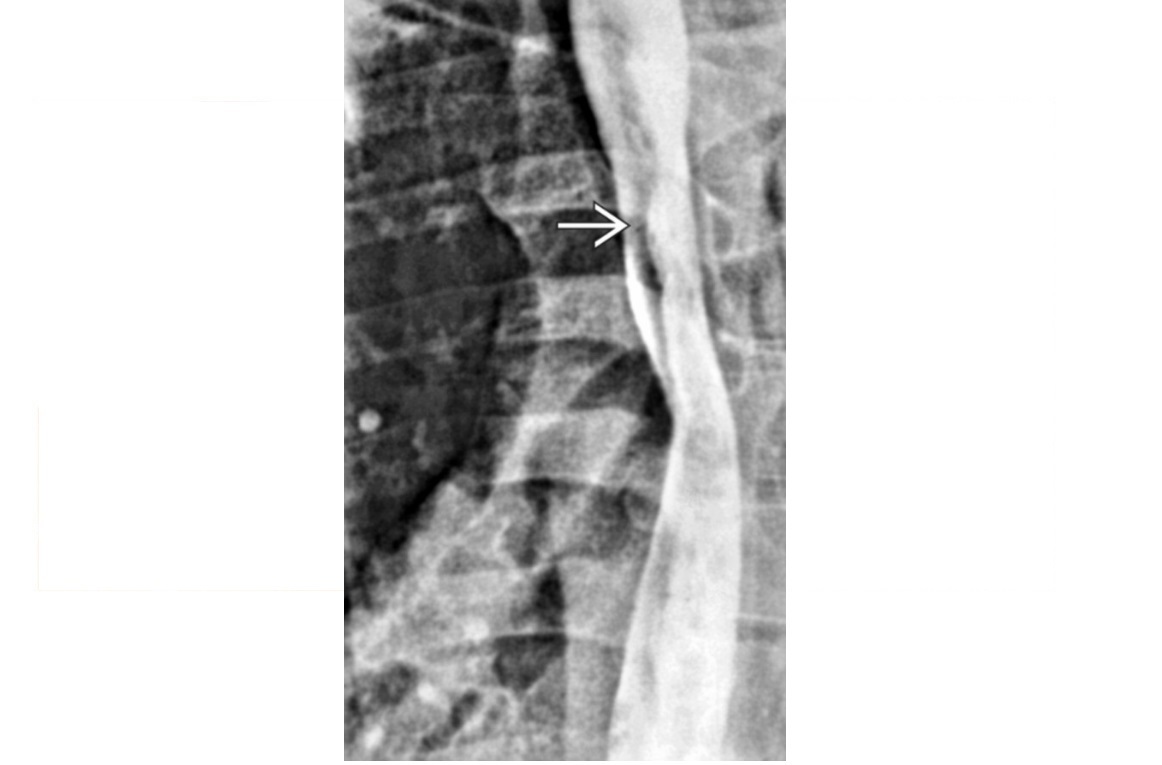

Chronic pancreatitis duct dilatation vs pancreatic malignancy duct dilatation?

CP - dilatation is irregular - Duct is <50% of the AP gland diameter Cancer - Dilatation is uniform - Duct is >50% of the AP gland diameter